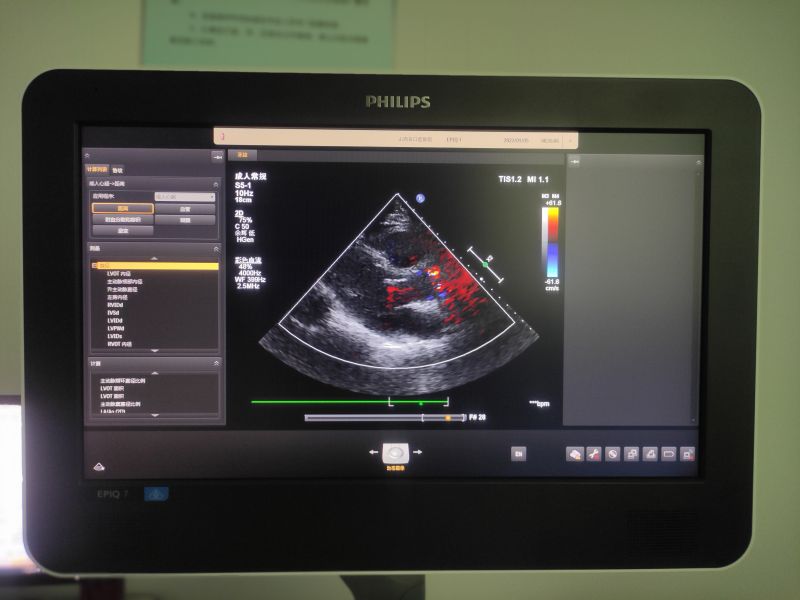

彩超檢查對受檢者無痛苦、無損傷、無放射性,檢查結果直接、快速且可重復使用,深受醫(yī)生及患者的歡迎。我院配備了業(yè)內高端的飛利浦EPIQ7彩色多普勒超聲診斷儀及圖文工作站,目前主要開展的診療范圍包括頭頸部(甲狀腺、血管、淋巴結等)、心臟、腹部(肝、膽、胰、脾、雙腎)、四肢血管等多個系統(tǒng)的檢查。其中,頸動脈B超是“三高”(高血壓高血脂高血糖)患者進行口腔有創(chuàng)操作前篩查高風險患者的重要輔助檢查項目。